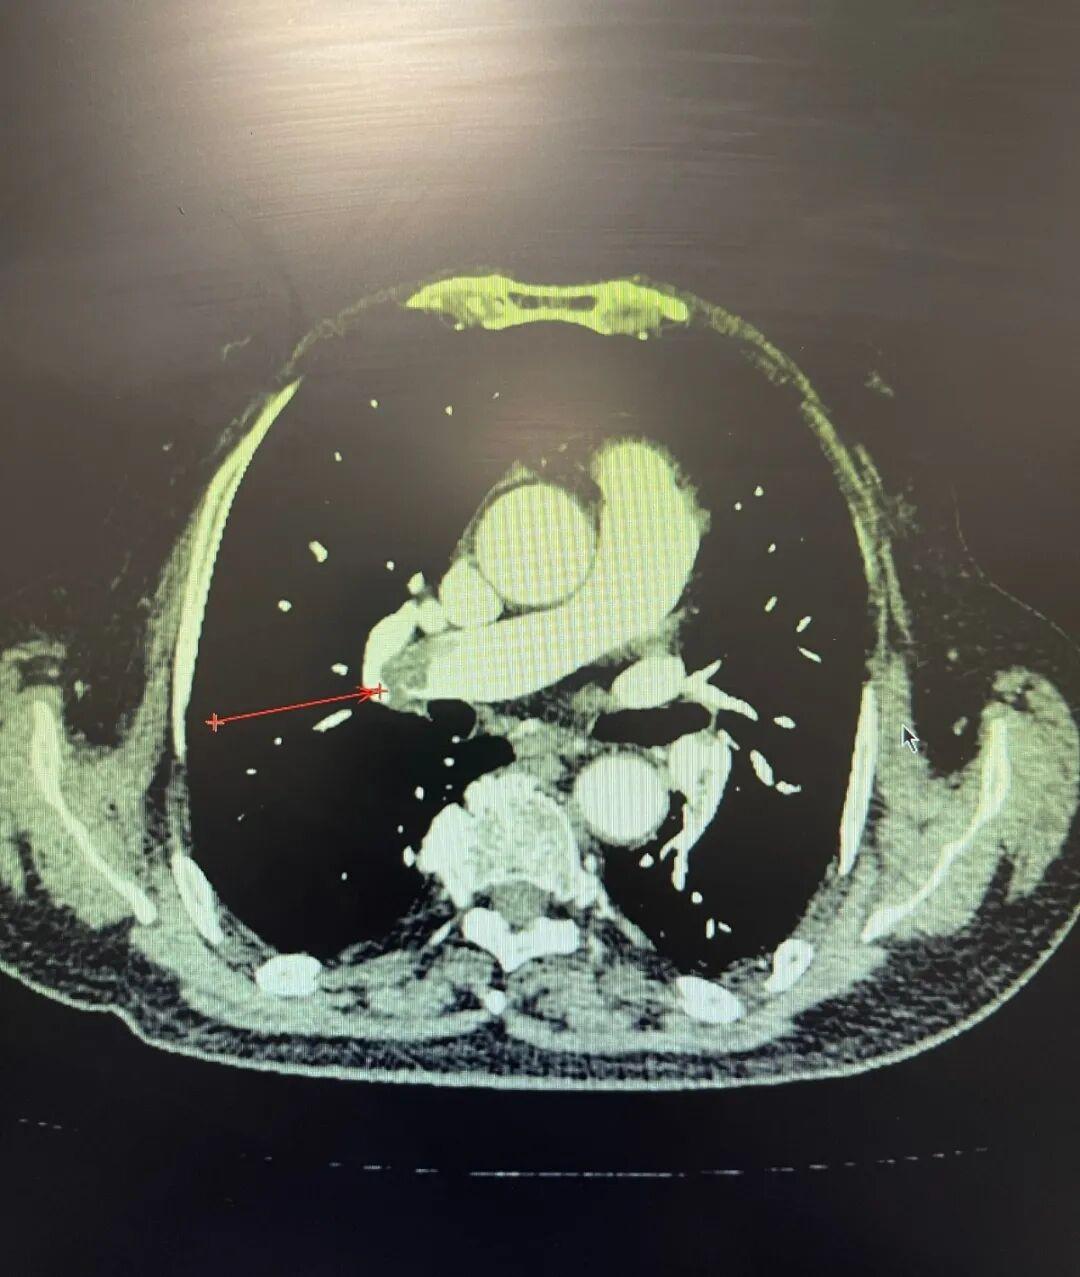

肺动脉CT血管成像清晰地显示,患者双肺动脉主干及几乎所有主要分支,都被大量血栓堵塞。

手术过程紧张有序。当取栓装置从患者右肺下叶动脉成功收回时,暗红色血栓被取出。即刻造影复查显示,原本几乎闭塞的血管恢复了通畅,血流影像显著改善。紧接着,手术团队又为她安全放置了一枚可回收的腔静脉滤器,在血液回流的通道上设置了一道安全滤网,以预防未来可能出现的血栓再次脱落风险。